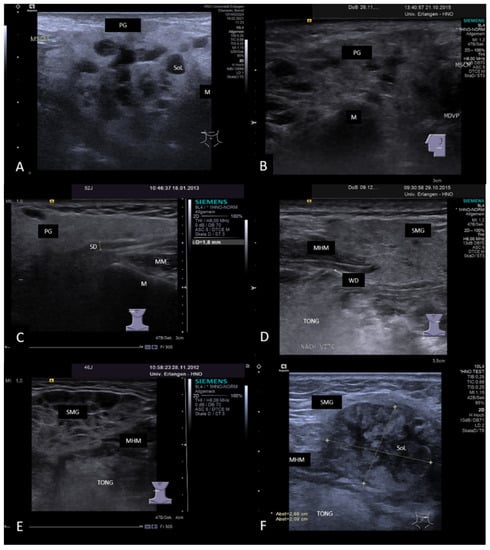

3.3. Ultrasonographic Signs of Acute and Chronic Inflammatory and Obstructive Sialadenitis

3.3.1. Acute or Subacute Primary Non-Obstructive Microbial Sialadenitis

3.3.2. Obstructive Sialadenitis Caused by Sialolithiasis

3.3.3. Non-Sialolithiasis-Caused Unspecific Sialadenitis with Sialodochitis and/or Duct Stenosis with Primary or Secondary Obstruction

3.4. Disease-Associated Inflammatory Sialadenitis with Sialodochitis (and Possible Secondary Obstruction)

3.4.2. Chronic Recurrent Juvenile Parotitis